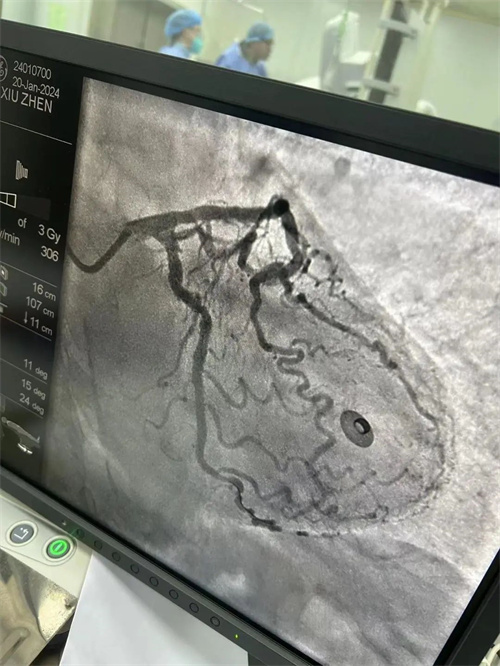

患者易婆婆(化名),70 岁,因突发胸痛被紧急送往犍为县中医医院。经过检查,易婆婆被诊断为急性心肌梗死,需要立即进行心脏支架植入手术。时间就是生命,犍为县中医医院介入诊疗中心医护团队迅速为易婆婆实施了手术。经过一个多小时的紧张手术,易婆婆的血管被成功疏通,症状即刻缓解。

![]() |

支架前